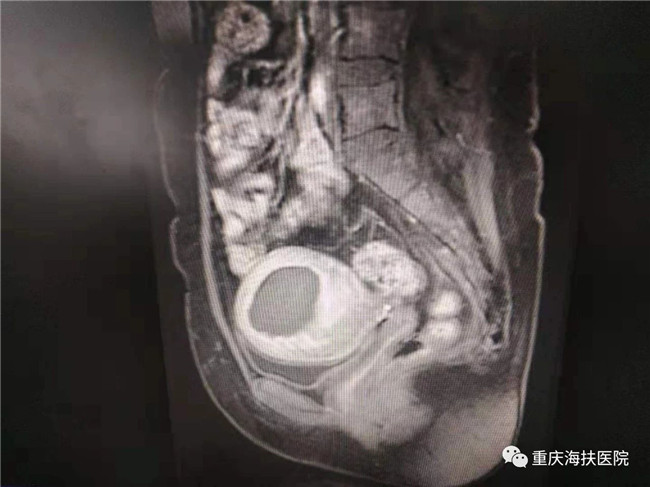

2019年9月18日,39歲的李女士在重慶海扶醫(yī)院微信群里向其主治醫(yī)師楚麗報喜:剖宮產(chǎn)一個6.2斤的海扶小公主!

2017年10月,李女士因子宮腺肌病到重慶海扶醫(yī)院就診,那時的她已經(jīng)被痛經(jīng)折磨了4年,疼痛評分(VAS)高達7-8分,嚴(yán)重影響正常生活、工作甚至睡眠,多地醫(yī)院建議切除子宮。

李女士因為有保留子宮和再生育的愿望,毅然選擇了不開刀、不流血的聚焦超聲消融手術(shù),術(shù)中消融病灶達6公分,消融效果良好。術(shù)后李女士發(fā)現(xiàn)自己的痛經(jīng)癥狀明顯緩解,并在1年后成功妊娠,于2019年9月18日剖宮產(chǎn)一個6.2斤的海扶小公主!